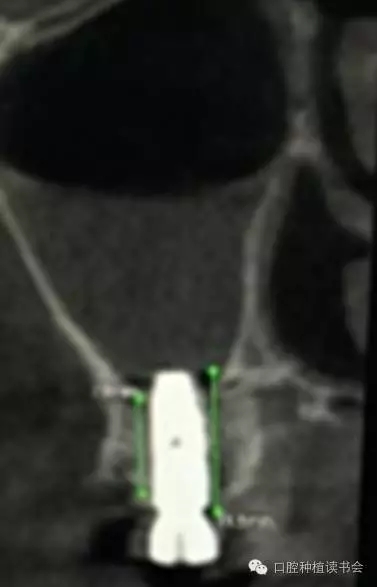

雖然牙槽脊垂直、水平吸收的程度幾乎相當,但是由于上頜后牙牙槽脊寬度較大,后牙區(qū)經(jīng)常出現(xiàn)圓鈍的、較寬的牙槽骨狀態(tài),臨床表現(xiàn)為剩余牙槽骨高度(Residual Bone Height,RBH)不足。在個別情況下,由于嚴重牙周病、根尖病等因素的影響,也會使牙槽脊水平寬度不足,表現(xiàn)為刃狀牙槽脊。上頜后牙一般為多根牙,當牙周病和根尖病到一定程度后,磨牙才開始松動導致不能保留,又因上頜牙槽骨骨密度較低,在有些病例,牙槽脊重度吸收,RBH甚至不足1mm(圖1)。

▲(圖1)